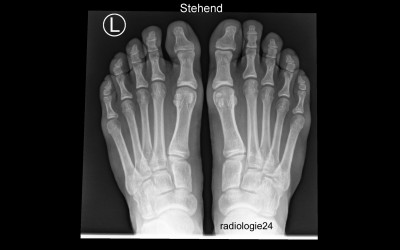

Radiologie-Quiz

Röntgenfall des Monats

Geben Sie Ihre Diagnose ab!